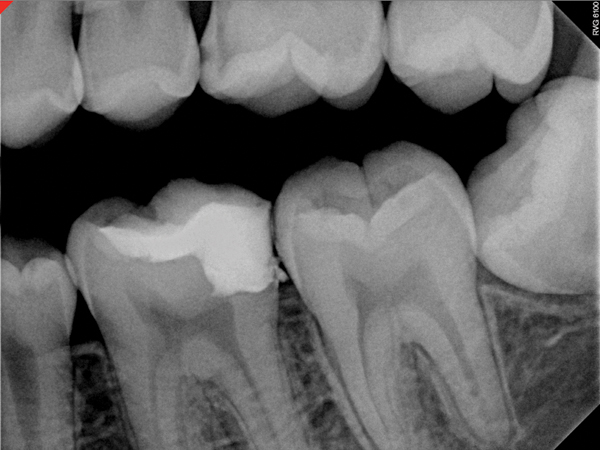

Figure 11. Preoperative radiograph. Courtesy of Dr. Guillaume Jouanny.

Figure 11

Figure 12. Postoperative radiography after full pulpotomy was performed. Courtesy of Dr. Guillaume Jouanny.

Figure 12

Figure 13. Tooth was asymptomatic at 1-year follow-up. Courtesy of Dr. Guillaume Jouanny.

Figure 13

In this case, the tooth tested vital but showed clinical signs of irreversible pulpitis. Treatment with a full pulpotomy was chosen to improve the chances the remaining pulp would survive and remain healthy. The preoperative radiograph in Figure 11 shows extensive caries in the tooth and a slightly widened apical periodontal ligament. A full pulpotomy was performed using the BC putty (Figure 12). After the putty set, a coronal restoration was placed, and an immediate postoperative radiograph was taken and viewed. At the 1-year follow-up, the tooth was asymptomatic, and the radiograph showed continued root development (Figure 13), a healthy apical periodontium, and, importantly, no calcifications in the remaining pulp (as is often seen with a calcium hydroxide therapy). A radiograph taken of the contra-lateral tooth showed similar root development (Figure 14).